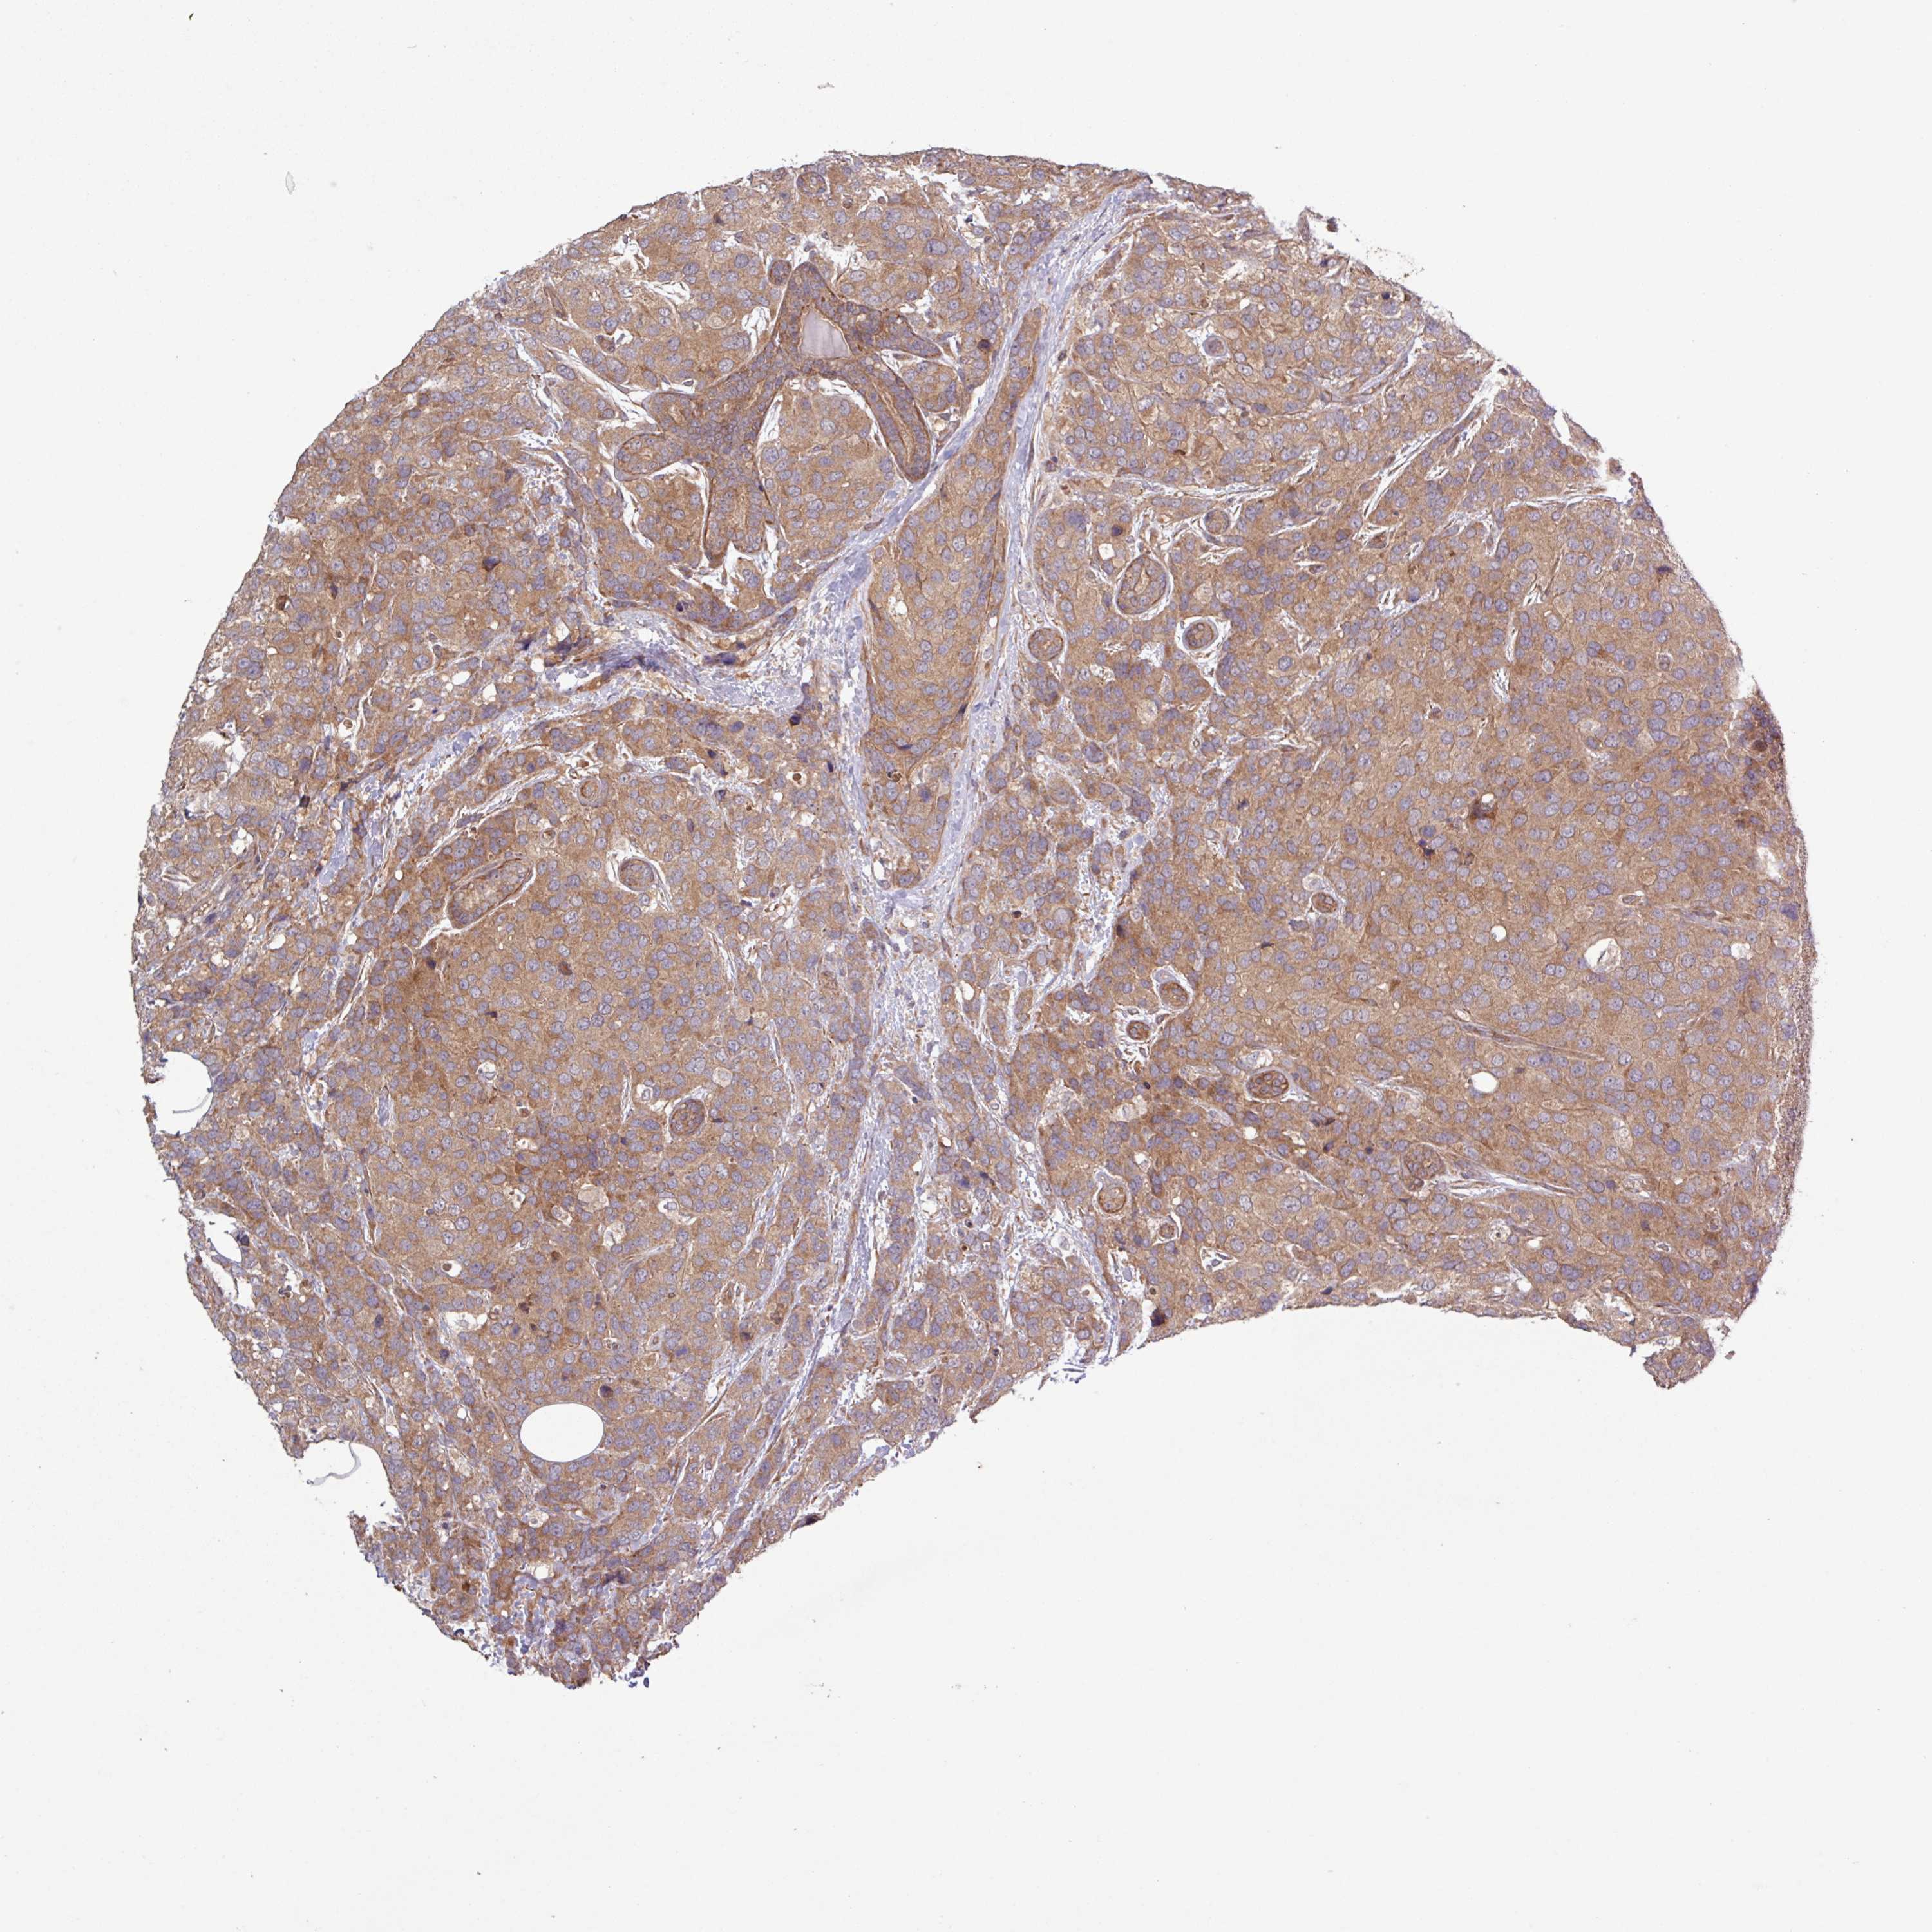

BRCA TCGA BRCA VALIDATION PROTEIN EXPRESSION

ANTIBODIES

AND

VALIDATION